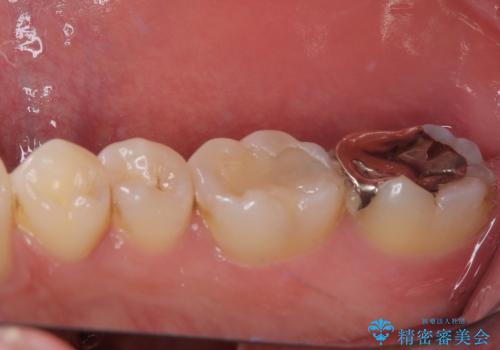

最後の確認方法として、局所麻酔を行わずに最後臼歯の銀歯を外し、神経組織近くまで歯質を切削したところ痛みなどを全く感じず、その後無菌的環境下にて切削を進めたところ、神経組織の一部が壊死していることが確認されました。

その後は速やかに根管治療を行い、初回の処置以降は痛みや違和感が一気に引いたため、根管治療後にオールセラミッククラウンにて補綴治療を行うこととしました。